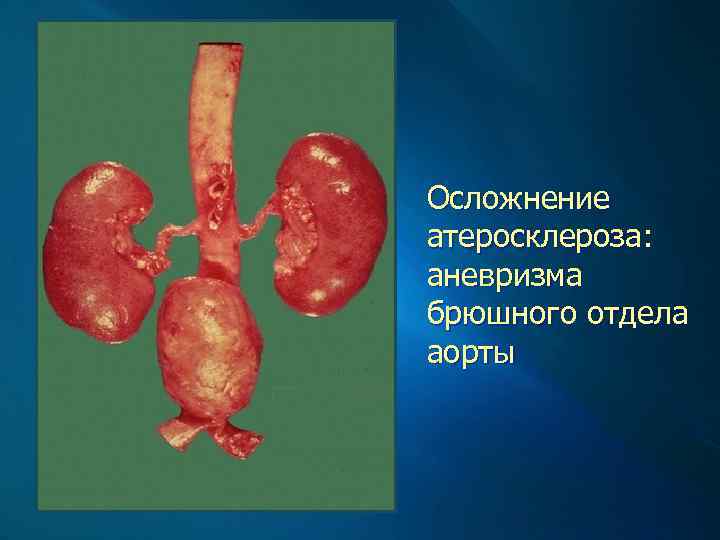

Клинические проявления и осложнения Атеросклероз аорты клинически значимых проявлений не имеет. Осложняется развитием аневризмы аорты, чаще в брюшном ее отделе, тромбозом в области ее бифуркации (синдром Лериша), эмболией (атероматозными и тромботическими массами) ее ветвей, что проявляется инфарктами почек и внезапной гипертензией и некрозами (инфарктами) кожи на пальцах стоп.

Осложнение атеросклероза: аневризма брюшного отдела аорты

Атеросклеротические аневризмы аорты